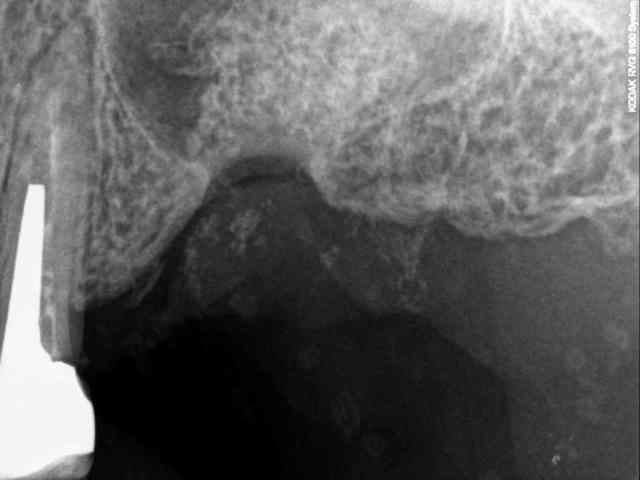

je dois pratiquer un rehaussement de plancher sinusien par volet latéral et je ne sais comment gérer le décollement de la membrane de Schneider au niveau de la communication bucco sinusale

Dès le départ, je m'inquiète au niveau du décollement du lambeau sur la CBS, on risque de déchirer à ce moment là

je joins quelques captures pour vous faire une idée